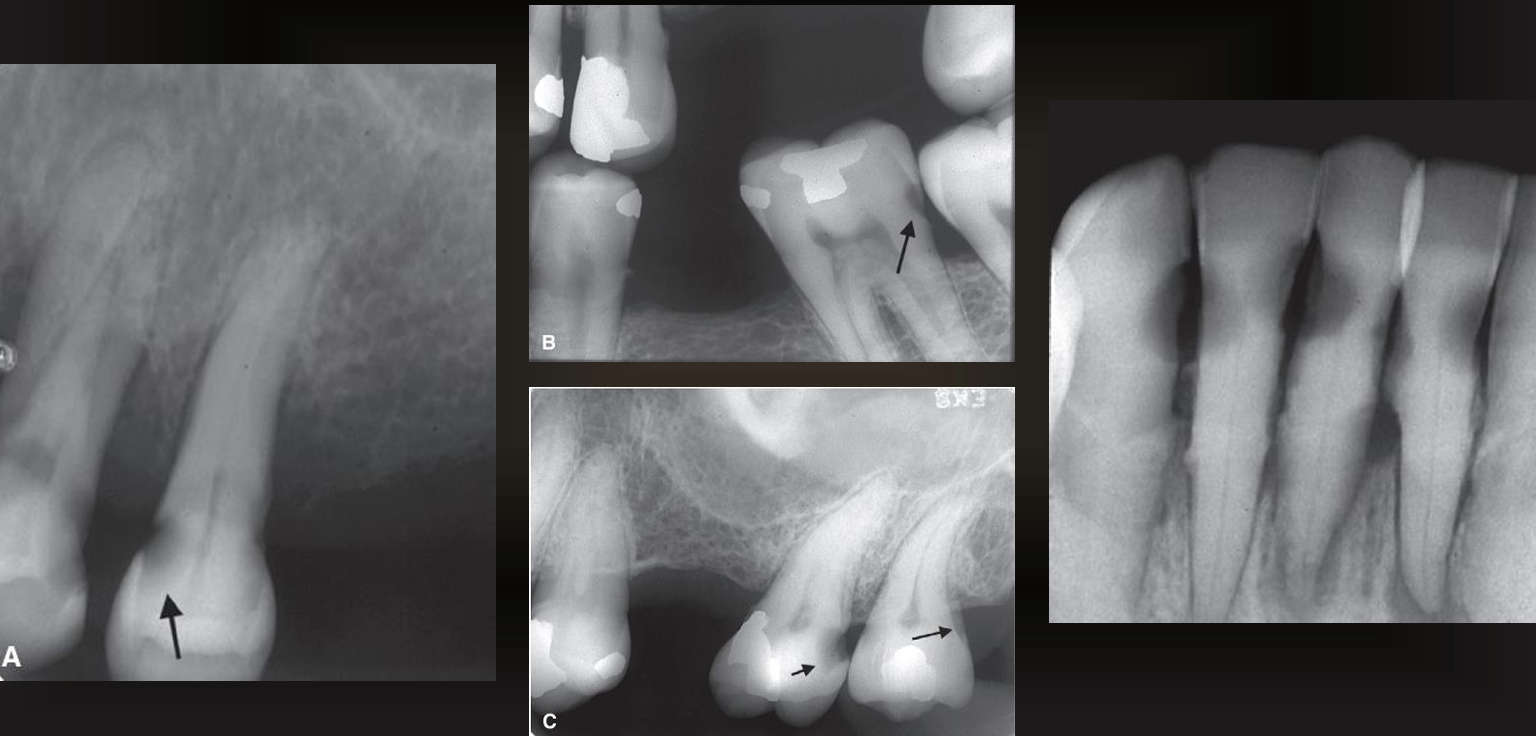

a?

class I, occlusal surfaces

b?

class II, proximal surfaces

c? left lol sorry

class III

c? right

class IV

d?

class V, buccal and lingual surfaces or root surfaces

e?

class VI

what are the arrows pointing to?

incipient interproximal caries

what do these images have?

interproximal caries (not incipient)